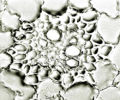

内部形態:鏡検

生姜(ショウキョウ、乾生姜)

JP15:内部形態についての記載はない。

- 生薬の性状

本品は偏圧した不規則な塊状でしばしば分枝する。分枝した各部はやや湾曲した卵形又は長卵形を呈し、長さ2~4cm、径1~2cmである。外面は灰白色~淡灰褐色で、しばしば白粉を付けている。折面はやや繊維性、粉性で、淡黄褐色を呈する。横切面をルーぺ視するとき、皮層と中心柱は明瞭に区別され、その全面に維管束及び分泌物が暗褐色の細点として散在する。 本品は特異なにおいがあり、味は極めて辛い。

- 産地による比較

| 生姜 <中国雲南省> | 生姜 <中国貴州省> | 生姜 <日本> | 生姜 <インド> |

|

|

|

|

| 維管束 | 維管束 | 維管束 | 維管束 |

|

|

|

|